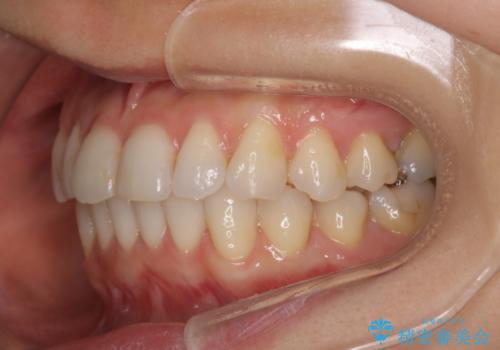

八重歯と前歯のガタガタをインビザラインで

- 八重歯と前歯のガタガタを主訴に来院されました。

目立たず矯正したいとのことでインビザラインで矯正することとしました。

インビザラインで目立たずに治療を終えることができ、喜んでいただけました。